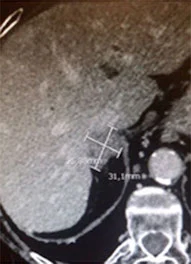

Un altro tipo di tumore del fegato, più raro, è il carcinoma fibrolamellare. Questa forma di cancro è generalmente diagnosticata in pazienti giovani e, rispetto al carcinoma epatocellulare, tende ad essere meno invasiva e a crescere in modo più ben delimitato. Una caratteristica distintiva del carcinoma fibrolamellare è la presenza di una lesione fibrotica centrale, visibile attraverso tecniche di diagnostica per immagini come la risonanza magnetica o la tomografia computerizzata (TC).